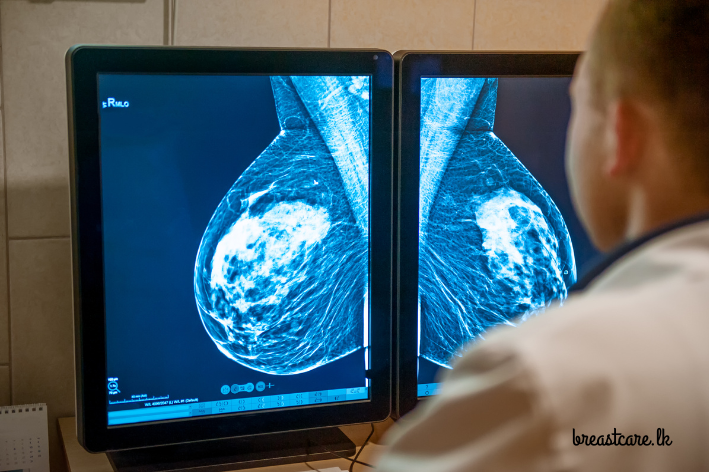

මැමෝග්රෑම් එකක් කියන්නේ පියයුරු වල ගන්න X-ray ඡායාරූපයක් . මේකෙන් කරන්නේ පියයුර ඇතුළේ තියෙන පුංචි වෙනස්කම්, ගැටිති, හෝ වෙනත් අසාමාන්යතා හොයාගන්න එකයි. මේවා සාමාන්ය පරීක්ෂණයකදී හෝ ස්පර්ශයෙන් හොයාගන්න බැරි වෙන්න පුළුවන්.මැමෝග්රෑම් පරීක්ෂණ වර්ග දෙකක් තියෙනවා:

- ස්ක්රීනින් මැමෝග්රෑම් (Screening Mammogram): මේක තමයි රෝග ලක්ෂණ නැති අයට, පිළිකාවක් තියෙනවද කියලා බලන්න කරන පරීක්ෂණය. සාමාන්යයෙන් අවුරුදු 40ට වැඩි කාන්තාවන්ට නිතිපතා ( අවම වශයෙන් අවුරුදු තුනකට වරක්මේ පරීක්ෂණය කරන්න නිර්දේශ කරනවා. මේකෙදි පියයුරු දෙකේම x ray පින්තූර ගන්නවා.

- ඩයග්නොස්ටික් මැමෝග්රෑම් (Diagnostic Mammogram): මේක කරන්නේ යම් රෝග ලක්ෂණයක් (උදා: ගැටිත්තක්, වේදනාවක්) තියෙනවා නම්, ඒක පිළිකාවක්ද කියලා බලන්න. මේකෙදි අවශ්ය නම්, අමතර ඡායාරූප හෝ පියයුරේ කොටසක් විතරක් zoom කරලා පින්තූර ගන්නවා.